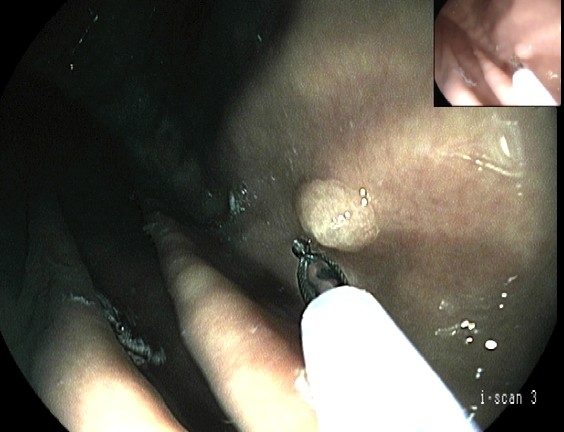

胃镜检查时常为圆形或类圆形隆起,良性息肉常<2cm,形状规整,表面光滑,色泽同周围黏膜或略红,多数无蒂,直视下活检及组织学检查有助于了解病理类型。

胃息肉可经胃镜下切除,有蒂息肉可用高频电凝电切,无蒂息肉科采取高频、激光、微波、氩气刀、射频、内镜黏膜下切除术(EMR)、内镜黏膜下剥离术(ESD)等方式治疗,息肉切除后预后一般良好。

内镜下圈套器电凝切除术